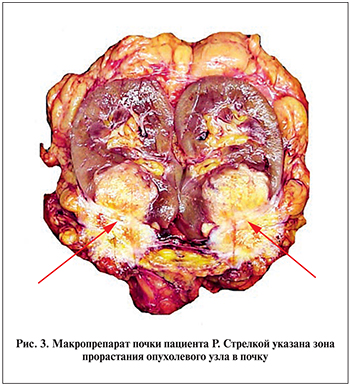

01.03.2018 пациент был прооперирован. В связи с выраженным спаечным процессом после предыдущей операции выполнен адгезиовисцеролизис. По передней поверхности нижнего полюса левой почки определялся плотный узел диаметром 4,4 см, прораставший в почку и боковую стенку живота. Второй узел размерами 3×3 см располагался в полости малого таза, прорастал в верхнеампулярный отдел прямой кишки, вовлекая семенные пузырьки с обеих сторон, семявыносящий проток справа и прилегал к правому мочеточнику в области его устья. Была проведена мобилизация оставшихся левых отделов ободочной кишки, поперечной ободочной кишки, левой почки. В связи с тем что не представлялось возможным исключить инвазию опухолевого узла в левую почку, было решено выполнить не ее резекцию, а нефрэктомию. Осуществлена мобилизация прямой кишки до нижнеампулярного отдела вместе с опухолевым узлом и вовлеченными с обеих сторон семенными пузырьками, правым семявыносящим протоком. В процессе мобилизации в связи с прилежанием опухолевого узла к правой стенке таза проведена перевязка внутренней подвздошной артерии в месте отхождения от общей подвздошной артерии. Ободочная кишка была пересечена проксимальнее ранее сформированного трансверзосигмоидного анастомоза на 1 см, прямая – на уровне среднеампулярного отдела, на 5 см дистальнее нижнего полюса опухоли. После этого макропрепарат единым блоком удален из брюшной полости. В левой мезогастральной области сформирована одноствольная трансверзостома. Таким образом, больному была выполнена комбинированная ререзекция левых отделов ободочной кишки, прямой кишки по Гартману, резекция семявыносящих протоков и двусторонняя везикулэктомия, нефроуретерэктомия слева с резекцией боковой стенки живота, одноствольная трансверзостомия (рис. 2, 3).

Гистологическое исследование удаленного препарата показало, что в прямой кишке имелась метахронная опухоль, имеющая строение умеренно дифференцированной аденокарциномы с глубоким изъязвлением, очагами некроза, периваскулярным и периневральным ростом с врастанием в брюшину, семенные пузырьки и окружающую их клетчатку, обрастанием семявыносящего протока с очаговым врастанием в его стенку. В 3 параректальных из 19 исследованных лимфатических узлах определены метастазы аденокарциномы с полным замещением лимфоидной ткани, очагами инвазии опухоли за капсулу узлов. Узел, вовлекший почку, расположен в основном экстраренально, был представлен опухолевой тканью аналогичного строения опухоли прямой кишки с врастанием в капсулу и паренхиму нижнего полюса почки и наличием опухолевых эмболов в ее сосудах. Сосуды ворот почки и мочеточник были интактными. Также определено врастание опухолевого узла в резецированные участки скелетных мышц передней брюшной стенки с инвазией сосудов.